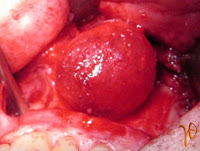

Μια άλλη περιοχή του στόματος που μπορεί να δέχεται μακροχρόνιο ερεθισμό είναι ο βλεννογόνος των φατνιακών αποφύσεων, δηλαδή τα νωδά ούλα που στηρίζουν τις ολικές οδοντοστοιχίες. Η αντιδραστική βλάβη που μπορεί έτσι να εκδηλωθεί ονομάζεται ινώδης πτυχωτή υπερπλασία (Εικόνα 8).

Εικόνα 8. α. Περίπτωση κάτω δεξιάς αντιδραστικής υπερπλασίας (βέλος) – στο ένθετο η βλάβη παρασκευασμένη πριν την αφαίρεση, β. Άλλη περίπτωση κάτω αριστερής αντιδραστικής υπερπλασίας.